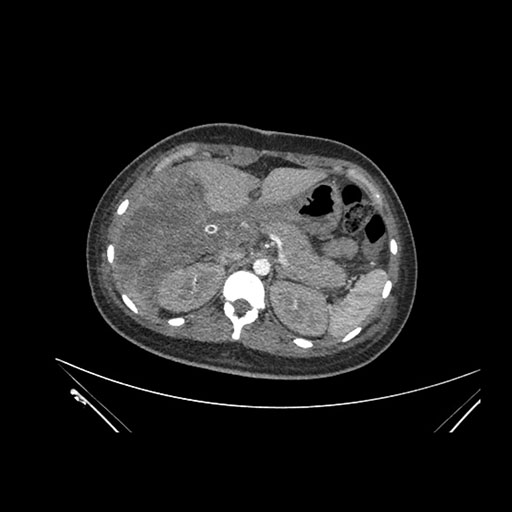

Axial Arterial

Imaging analysis

Based on initial findings, which issue(s) would you be most concerned about?